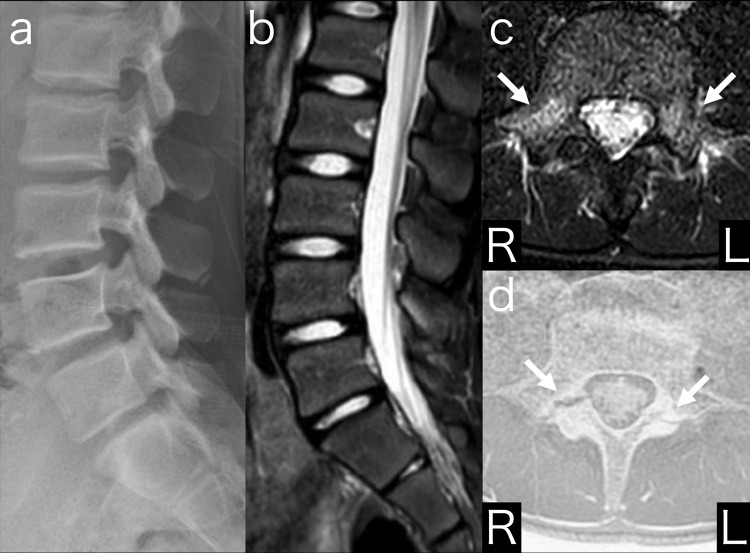

Multiple computed tomography (CT) scans are required to diagnose lumbar spondylolysis stage and confirm fusion degree. However, multiple CT scans should be avoided because of radiation exposure. There are no case reports of complete diagnosis and treatment of pediatric lumbar spondylolysis without the use of CT. Fast field echo resembling a CT using restricted echo-spacing (FRACTURE) is a magnetic resonance imaging (MRI) sequence used to evaluate bone lesions. Here we report the case of a pediatric patient with lumbar spondylolysis who was able to return to sports after diagnosis, treatment, and bone union confirmation using MRI and FRACTURE.